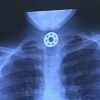

목구멍에 부품 걸려…10살 딸 잡을 뻔한 ‘피젯 스피너’

2017-05-20 나우뉴스 -